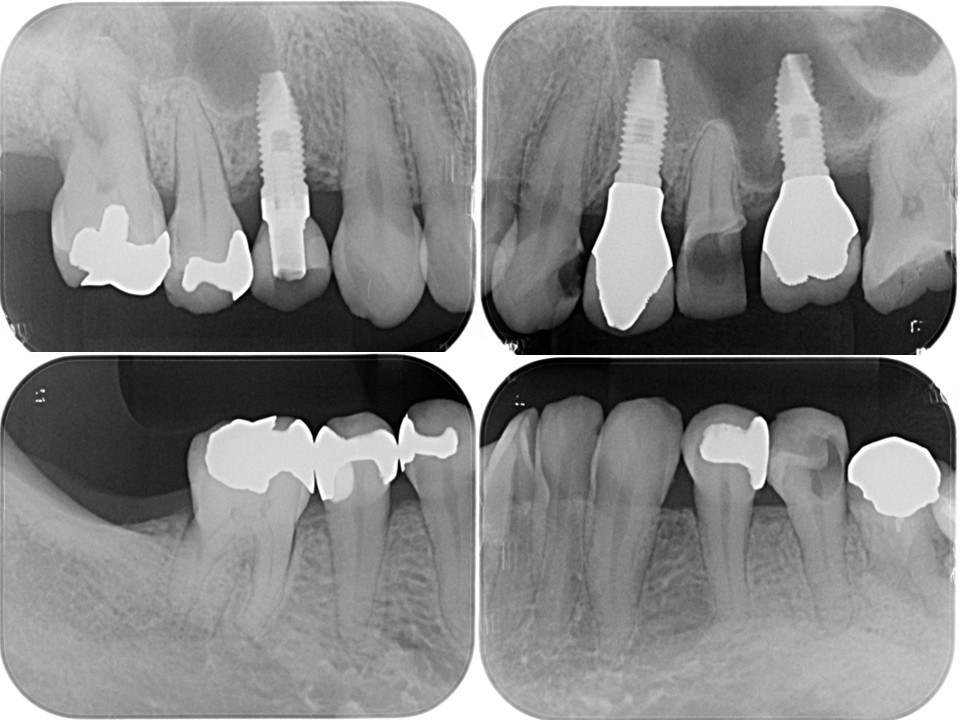

(図20)

う蝕が大きく進行した右上5番、左上3・5番、右下5番、左下5番、右上5番、左上3・5番、左下5番の隣在歯としてインプラント治療を予定しており、感覚受容器が乏しいエリアになることが理由でVPTにより有髄歯で保存することを目指した

(図21)右上5番の治療経過

近遠心にインプラントが存在し、右上5番が有髄歯で存在することで感覚受容器を正常な状態で保てている

(図22)左上3・5番の治療経過

左上5番も近遠心にインプラントが存在し、左上5番が有髄歯で存在することで感覚受容器を正常な状態で保てている

(図23)左下5番の治療経過

遠心にインプラントが存在し、左下5番が有髄歯で存在することで感覚受容器を正常な状態で保てている

(図24)右下5番の治療経過